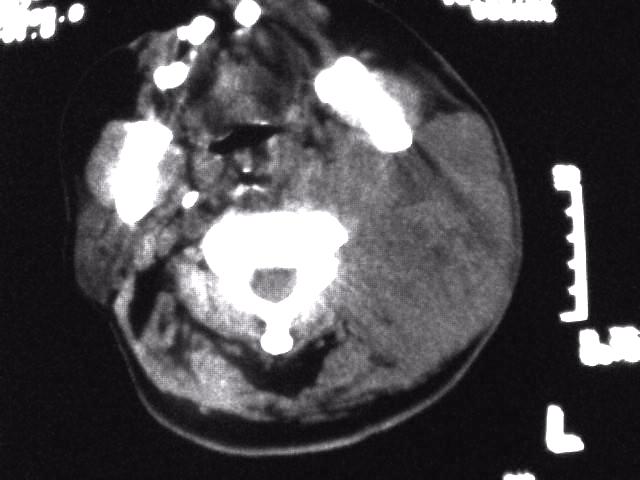

颈部层厚10mm间距10mm连续扫描及增强扫描共24层示:左侧下颈部胸锁乳突肌内侧区域内可见多发软组织结节,密度不均,内可见斑片状低密度区,大小不等,部分融合成块,左侧融合成一块者大约9.0x5.4,与周围肌肉、血管等结构界面不清,骨质未见明显浸润影。左侧锁骨下可见多个软组织结节,与周围界限尚清,左侧锁骨上窝内可见一大软组织肿物,大小约4.7x3.7cm,内密度欠均匀中心可见低密度区。

考虑:左侧颈部及双侧锁骨下多发淋巴结肿。非何杰金氏淋巴瘤可能性大,建议进一步检查。